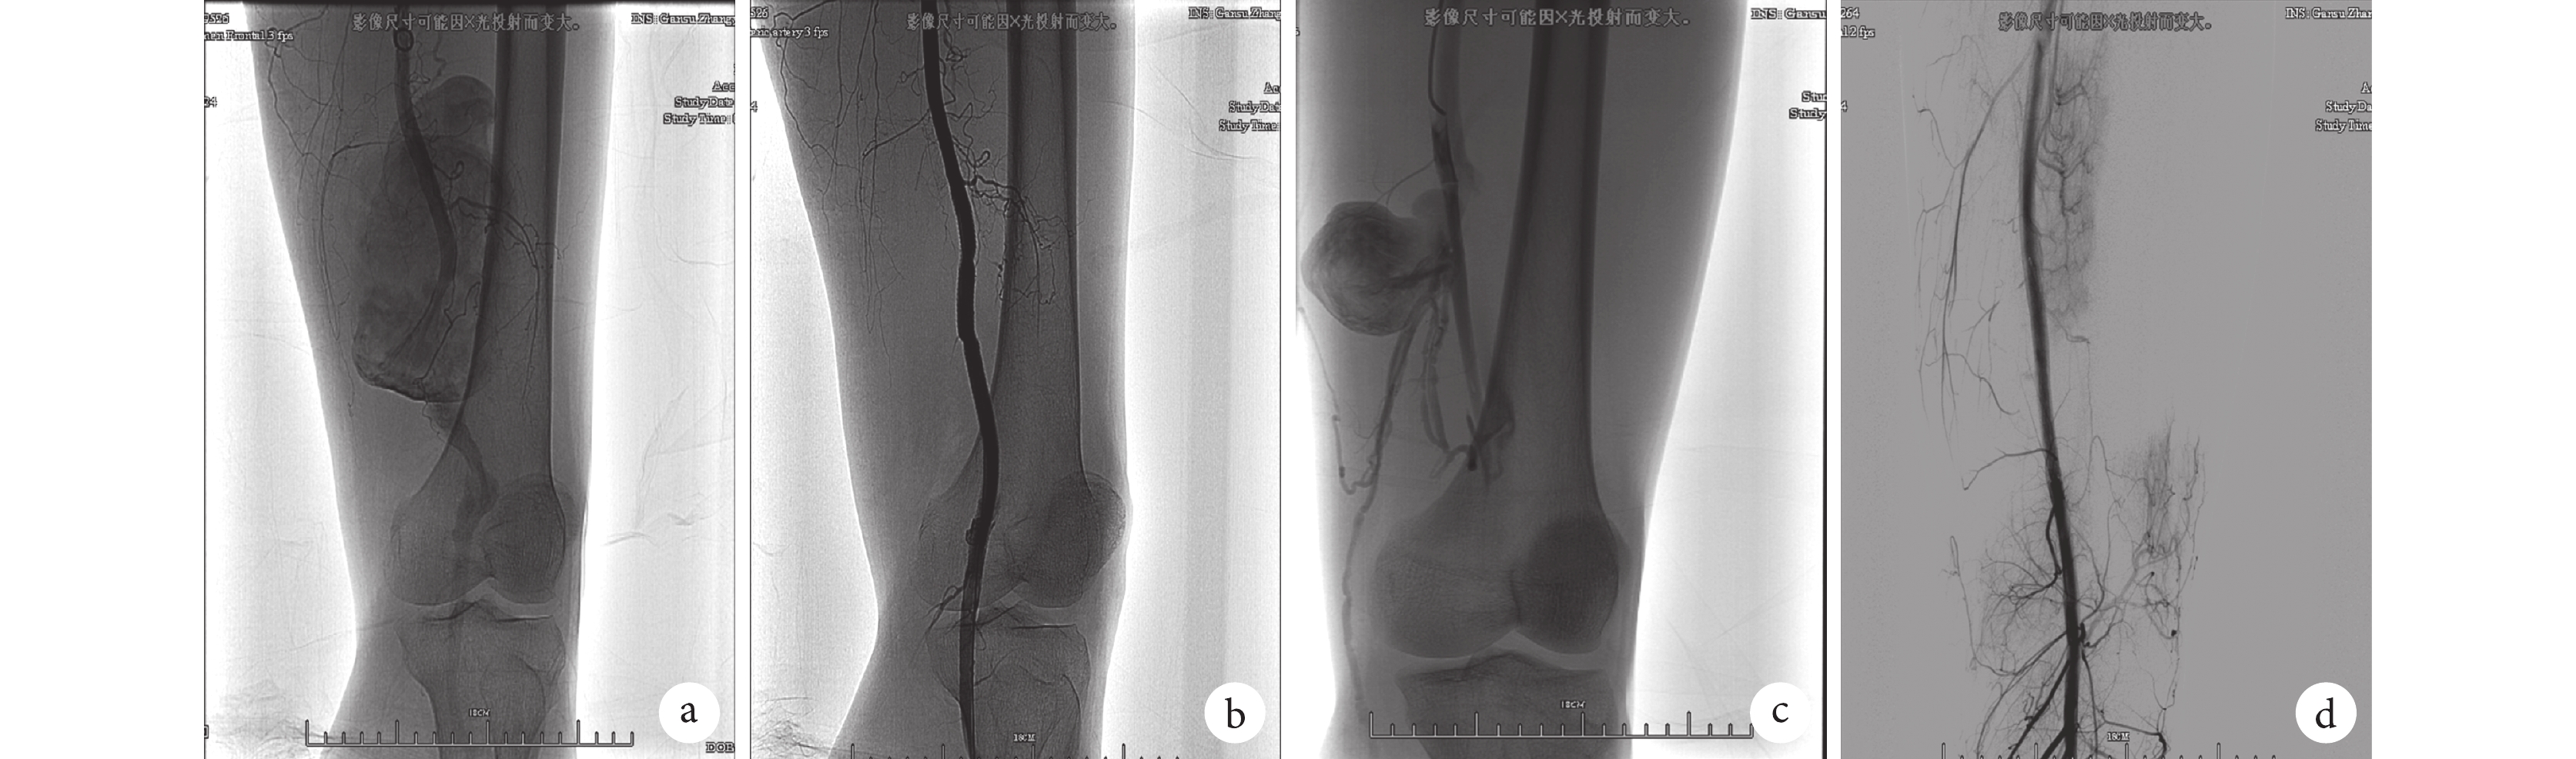

全組患者均一次支架釋放成功,無手術死亡。支架置入術后造影結果顯示:下肢動脈假性動脈瘤及動-靜脈瘺均得到覆膜支架修復,股動脈遠端血流通暢,流速增快,無內瘺發生。20 例下肢疼痛患者足背動脈搏動恢復且搏動較支架置入術前增強,疼痛即刻緩解;6 例患者股深動脈封閉。所有患者術后均皮下注射低分子肝素鈣(5 000 U,2 次/d),同時口服華法林 3 mg/d,每天監測凝血功能,當國際標準化比值(INR)達到 2~3 之間后停止注射低分子肝素鈣。術后 1 周內有 4 例患者出現發熱,體溫 37.5 ℃~38.9 ℃,均經抗感染等對癥處理后好轉;4 例血腫切開引流術患者及 2 例假性動脈瘤腔內穿刺抽液患者無并發癥發生。患者出院后均口服華法林抗凝治療(治療期間監測 INR 維持在 2~3 之間)6 個月后停止抗凝治療,所有患者術后 6 個月時行彩超檢查,12 個月時行下肢 CTA 檢查,結果均提示無假性動脈瘤復發及支架移位、變形、斷裂、支架內栓塞及內瘺發生。所有患者術后無下肢疼痛、間歇性跛行等癥狀。典型病例支架置入前后的影像學改變見圖 1。

a:術前股動脈造影顯示股動脈巨大假性動脈瘤;b:覆膜支架置入術后造影顯示股動脈巨大假性動脈瘤完全隔絕;c:術前股動脈造影顯示股動脈假性動脈合并動-靜脈瘺;d:覆膜支架置入術后造影顯示股動脈假性動脈瘤完全隔絕,動-靜脈瘺同時治愈